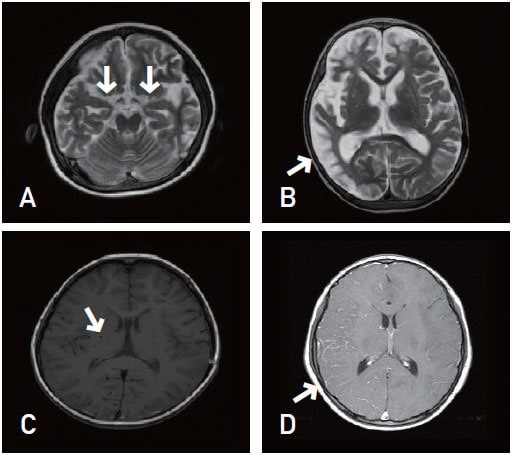

모야모야병은 뇌기저부의 주요 혈관이 서서히 협착되고 막히면서 뇌혈류가 감소하는 만성 진행성 뇌혈관 질환입니다. 협착이 진행된 부위를 대신해 뇌는 생존을 위해 얇고 약한 혈관망을 만들어 혈류를 보충하려 하고, 이 새로운 혈관들이 촬영 영상에서 연기처럼 퍼져 보인다고 하여 ‘모야모야’라는 이름이 붙었습니다. 기전적으로는 내경동맥 말단부와 중대뇌동맥·전대뇌동맥의 기시부에 병변이 가장 잘 생기며, 시간이 지남에 따라 양쪽에 대칭적으로 나타나는 특징을 보였습니다. 이 질환은 단순한 혈관 협착이 아니라 진행성 변화이기 때문에 치료하지 않으면 혈류 부족이 심해지고 뇌 손상이 누적될 수 있습니다. 또한 뇌기능이 체력·호흡·체온 변화 등에 민감하게 반응하기 때문에 과호흡, 울음, 격렬한 운동, 감염 등으로 증상이 악화될 수 있습니다. 즉, 모야모야병은 시간이 지나면서 뇌혈류를 감소시키고 뇌졸중 위험을 높이는 질환이며, 평생 관리가 필요한 만성적 특성을 갖고 있습니다.

따라서 가족력이 있거나 의심되는 증상이 있다면 뇌 MRA·MRI 등의 정기검진이 도움이 되며, 조기 진단 시 치료 효과도 훨씬 높아집니다.